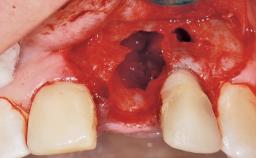

Immediate Flapless Placement of an Implant in a Maxillary Left Central Incisor Site

A 29-year-old female patient presented for treatment to replace the upper left central incisor tooth with an implant- supported restoration. The tooth had been intermittently symptomatic for the previous 12 months. The tooth had originally suffered trauma about 15 years previously. Several endodontic treatments had been performed, including an apicectomy procedure to retain the tooth. The patient was healthy and a non-smoker. She had reasonable expectations in regard to esthetic outcomes and the risk of marginal tissue recession following treatment. At medium smile, the gingival margins of the upper teeth were visible, with a display of 3 to 4 mm of the gingival margins. Gingival recession of tooth 21 and a discrepancy in the gingival levels between teeth 11 and 21 was observable during normal speech and smile.

Soft Tissue Anatomy Intact Defective

Socket Integrity Damage to one or more bone walls

Bone Volume Damage to one or more socket walls